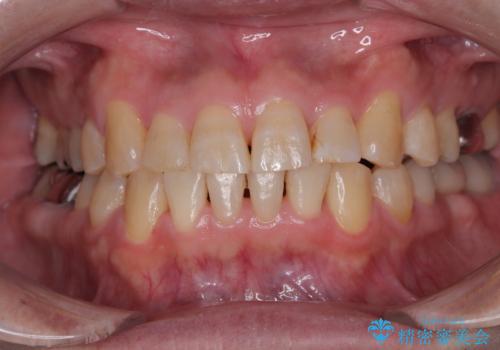

- 他院で矯正治療を終えた結果、下顎前歯の歯肉が退縮してしまい、歯根が見えていることが気になるとのことで来院された患者様です。

歯肉退縮に対して、上顎からの結合組織移植術(CTG)により、歯根の被覆を行うとともに、歯肉の厚みを増すことで将来の退縮リスクを抑制することとしました。

一度の処置で十分に根面被覆ができました。